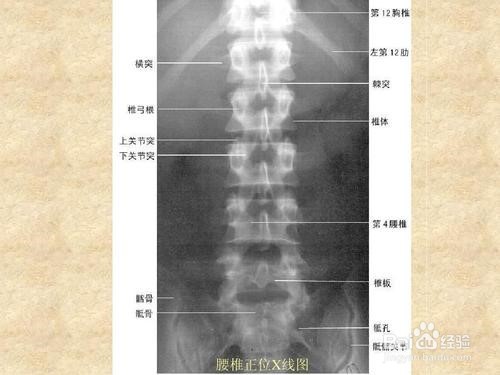

3、不同人体组织结构,根据其密度的高低及对X线的吸收的不同可分为三类。高密度,有骨骼和钙化,在X线片上显示为白色。中等密度,有肌肉,内脏,结缔组织,软骨和液体等,在X线片显示为灰白色。低密度,有脂肪和气体,在X 线片显示为灰黑色和深黑色。

6、X线临床诊断。运动系统:四肢骨折,脊柱骨折的分型,关节结构,异位骨化,髋关节脱位,半脱位,颈椎术后咽后壁脓肿,等等,这些疾病可用X线诊断。运动系统疾病在X线临床诊断中最常见。